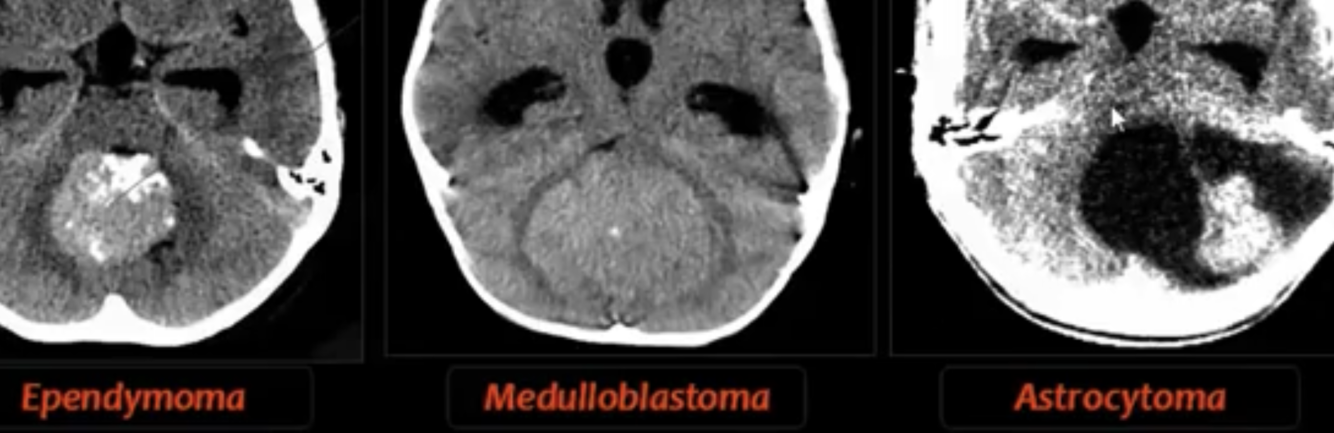

4TH VENT OBSTRUCTION:

-causes?